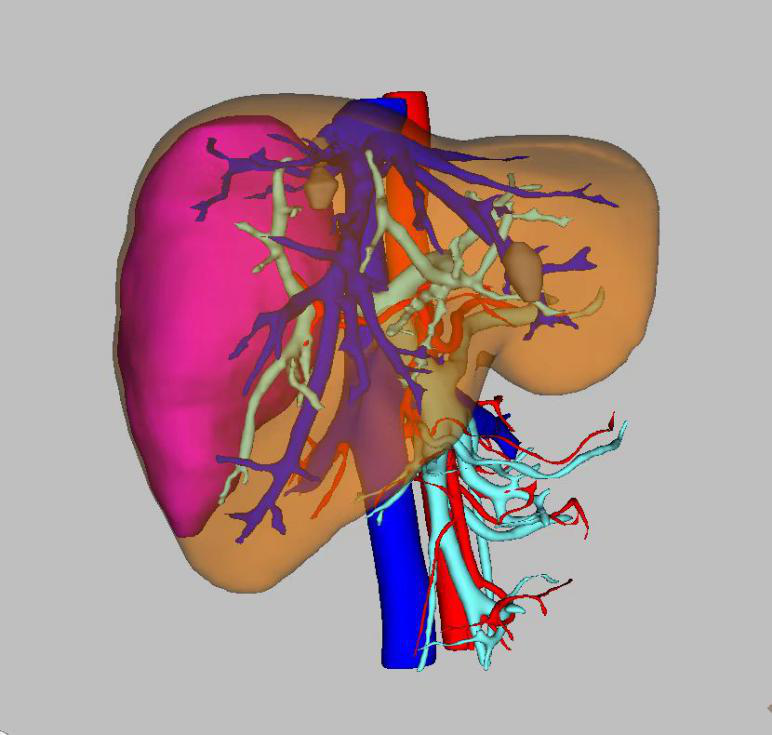

41歲的患者顏某,2月前在體檢檢查中發現肝占位性病變,但并未給予特殊治療,近日患者右上腹部隱痛不適頻繁發作,遂來我院就診。行腹部增強CT檢查后,診斷為肝血管瘤,肝膽胰外科陶銳主任醫師組織團隊謹慎地討論了顏女士的病情,經三維可視化重建技術將腫瘤行重建后,最終決定以腹腔鏡的形式切除血管瘤。

(圖示中紅色部分為肝血管瘤所在位置及體積)

手術由陶銳主任醫師主刀,帶領安代紅副主任醫師、張超超主治醫師,及麻醉護理團隊,經過3個多小時的緊密協作,順利將顏女士體內的血管瘤切除。